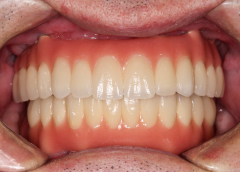

• Tình trạng mất răng:Mất hết răng cả 2 hàm và tiêu xương nặng.

• Phương hướng điều trị:Cấy ghép Implant All On 6 cho cả 2 hàm và phục hình răng sứ cố định.

• Trụ Implant sử dụng:Implant Mis C1 Đức

• Răng sứ sử dụng:Răng toàn sứ Nacera Pearl Đức

• Cấy 2 hàm All on 6 Implant Mis C1 Đức

• Phục hình răng toàn sứ Nacera Pearl Đức

Để đáp lại sự tin tưởng của chú Tùng, đội ngũ I-Dent đã nỗ lực giúp chú kiến tạo hàm răng mới chắc khỏe, thẩm mỹ hơn. Và kết quả sau cùng khiến chú rất hài lòng, khi có thể ăn uống thoải mái như lúc chưa mất răng.